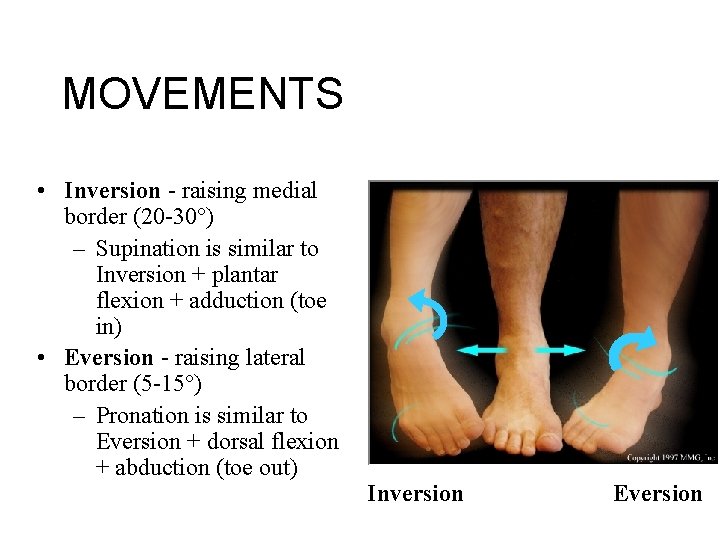

MOVEMENTS • Inversion - raising medial border (20 -30°) – Supination is similar to Inversion + plantar flexion + adduction (toe in) • Eversion - raising lateral border (5 -15°) – Pronation is similar to Eversion + dorsal flexion + abduction (toe out) Inversion Eversion